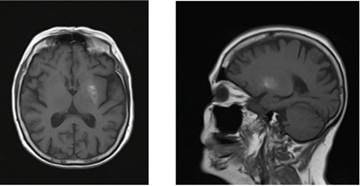

La resolución clínica completa es característica,2 especialmente con la instauración precoz del tratamiento.5 El tiempo puede ser variable, en días o meses.2,6 Los cambios de señal en la neuroimagen también son reversibles en la evolución, en promedio 180 días para la RM.6

Ambos casos presentados en este artículo, tienen la particularidad de que no lograron la mejoría completa. Creemos que la causa de la no mejoría total en el primer paciente fue la persistencia del mal control metabólico al alta, por lo que se mantuvo el mecanismo fisiopatológico de injuria al estriado. Mientras que el segundo caso presentó una mejoría inicial al lograr un adecuado control metabólico, presentando luego una peoría sintomática, no quedando clara la causa. Se debería buscar una explicación alternativa a la persistencia de la corea en el caso 2 (por ejemplo la posibilidad de daño estructural permanente o citar bibliografía de pacientes que no hayan revertido o posibilidad de que revierta-mejore en el futuro: mejoría tardía)